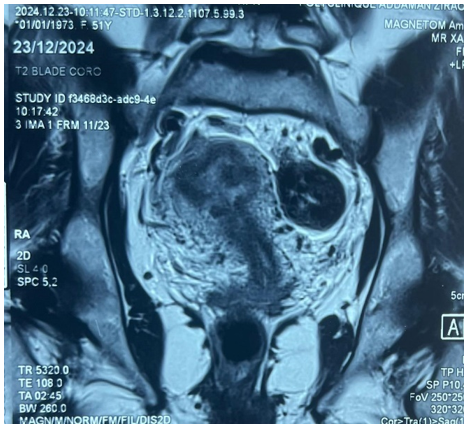

Pelvic MRI showed a predominantly solid left ovarian mass measuring 67 x 54 x 53 mm, classified as ORADS 4, with an additional submucosal myoma measuring 20 x 21 mm (Figure 2). CA-125 level was 18.25 IU/mL.

Figure 2: Frontal MRI view showing a predominantly solid left ovarian mass measuring 67x54x53 mm.